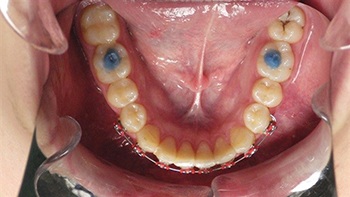

Figs. 3-4: Initial Appointment

Figs. 5-6: One-week follow-up showing early alignment after placement of brackets and light NiTi wire.